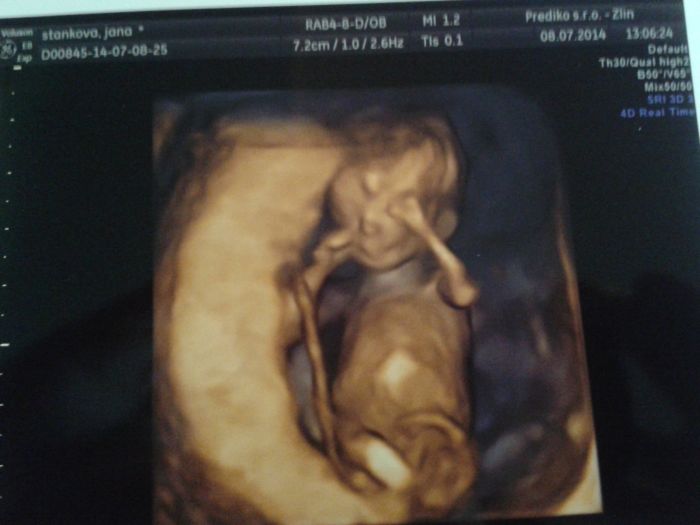

tak ja se taky podelim o naseho mimiska, jen nevime stale co to bude. dalsi kontrolu mam 22.8 tak doufam ze se ukaze ;-D